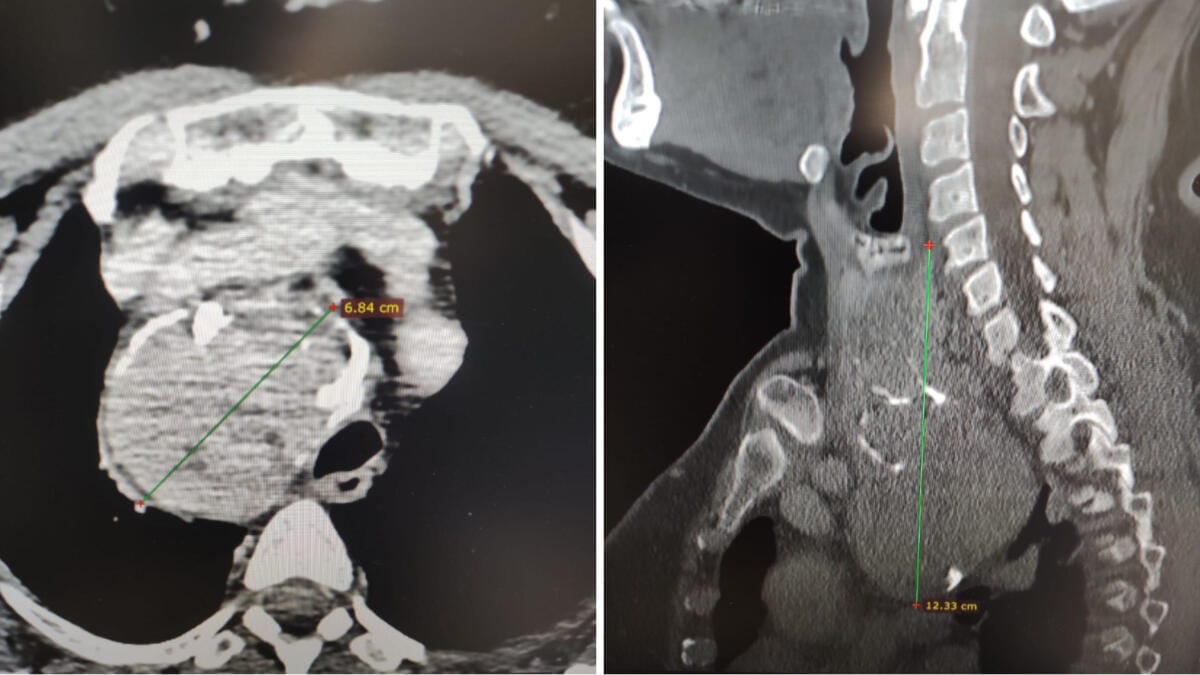

La paziente aveva un gozzo plongeant (o endotoracico) di circa sette centimetri. Da cinque anni, la 65enne aveva notato la massa nella parte anteriore del collo e un calo della voce. Il disturbo era dovuto alla pressione esercitata dal gozzo sul nervo che la controlla.

Gli accertamenti radiologici, spiega il dottor Luigi Madami, otorinolaringoiatra che ha eseguito l’intervento nell’Unità operativa diretta dal professor Nicola Quaranta, «hanno mostrato che la tiroide era ingrandita, con un’estensione di circa sette centimetri, si estendeva nel mediastino (la parte alta del torace) e spingeva la trachea verso sinistra, pur lasciandola libera nel passaggio dell’aria. Erano presenti anche piccoli noduli e calcificazioni».